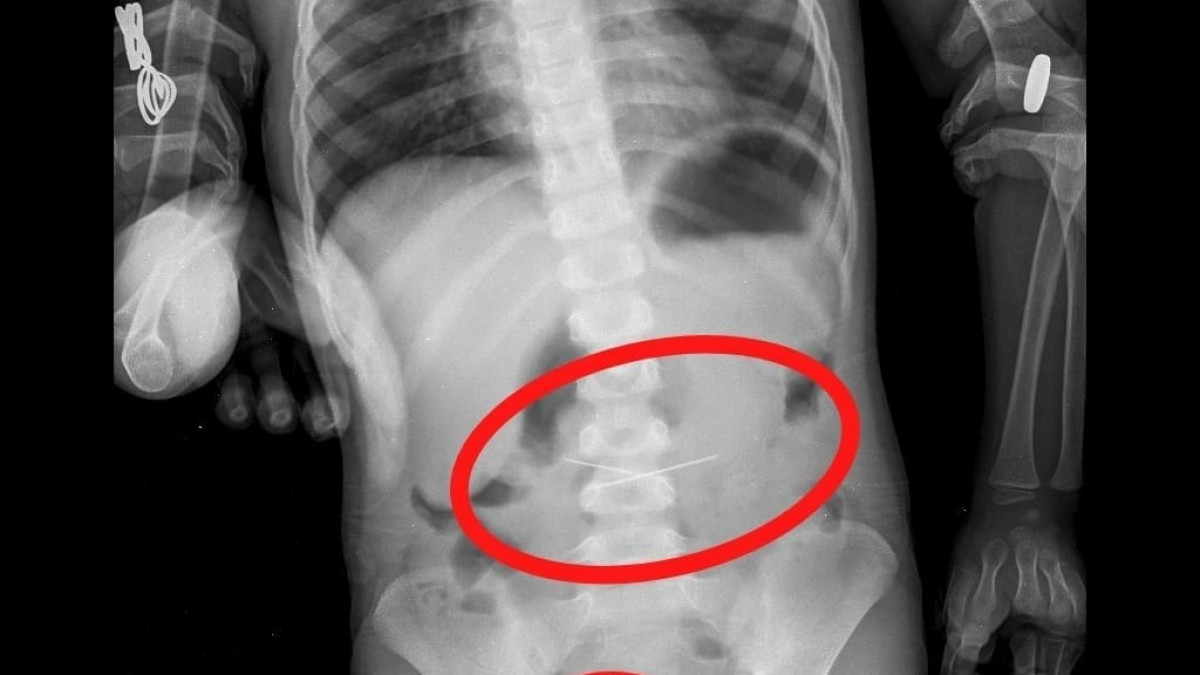

Таразда 3 жасар бала бірнеше ине жұтып қойған Тараздық дәрігерлер ине жұтып қойған үш жасар баланы аман алып қалды, — деп хабарлайды Бақ-Орда. Облыстық көпбейінді балалар ауруханасының қабылдау бөліміне баласы киім бөлшегін (бегунок) жұтып қойды деген шағыммен анасы келген. Кішкентай науқастың емін бас дәрігердің орынбасары Сейдахмет Шыныбеков пен Мәулім Кенжеәлі жүргізген. Дегенмен қарапайым рентгенографияда киім бөлшегінен (бегунок) бөлек, асқазан-ішек жолдарында тағы да төрт иненің бары белгілі болды. Қайтадан ЭФГДС жасалып, асқазаннан ине алынып тасталды. Содан кейін колоноскопияның көмегімен сигма тәрізді ішекке қадалған ине алынып тасталады»,-деді жоғары санатты хирург-дәрігер Сейдахмет Байдуллаұлы. Бала бақылауда болған. Іштің бақылау R–граммасында жамбас проекциясында төртінші ине табылды. Колоноскопия жасалып, ішектің шырышты қабығына қадалған сигма тәрізді ішектен соңғы ине алынып тасталды. Қазіргі уақытта қанағаттанарлық жағдайда бала үйге шығарылды.